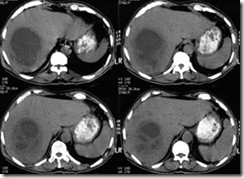

pemeriksaan radiologi metastases